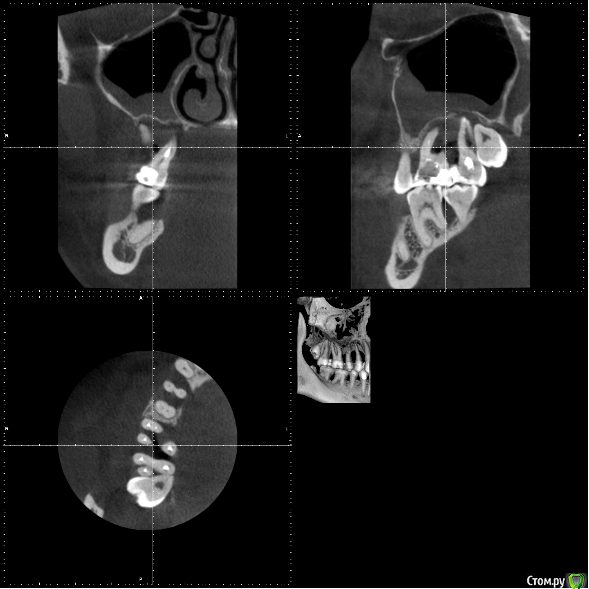

Pacient1234 Опубликовано 26 апреля, 2017 Поделиться Опубликовано 26 апреля, 2017 Уважаемые профессионалы, подскажите пожалуйста.Проблема: тяжелый хронический пародонтит, шатаются жевательные верхние зубы (зашинированы). По результатам КТ – отсутствие костной ткани на этом участке. Из-за этого хирург-имплантолог сказал, что мне нельзя делать ни синус лифтинг, ни имплантацию – бесполезно, имплантаты в итоге не приживутся, только выброшу деньги на ветер. Честно говоря, меня это слегка озадачило.. Действительно ли такое может быть, что костная ткань отсутствует настолько, что никакие методы ее нарастить невозможны (или возможны, но есть большая вероятность, что не получим положительный результат имплантации)?Еще больше меня волнует вопрос, как будет дальше развиваться моя ситуация. Как я понимаю, рано или поздно шатающиеся зубы выпадут и меня ждет съемный протез. Что при этом будет происходить с костной тканью? Какие риски такой стратегии?Спасибо! Ссылка на комментарий